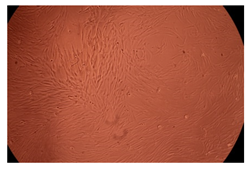

2.4. In Vitro Cytotoxicity Analysis

| Control |  |  | |

| Cop B | 10 µg/mL |  |  |

| 50 µg/mL |  |  | |

| 100 µg/mL |  |  | |